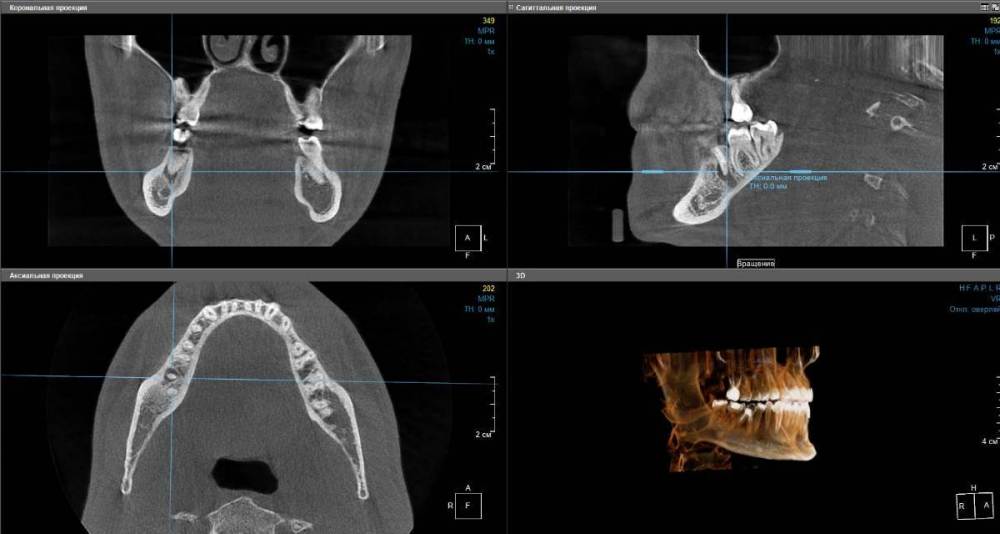

Artooth Опубликовано 9 июля, 2022 Поделиться Опубликовано 9 июля, 2022 (изменено) Правая нижняя шестерка (46), зуб был депульпирован более десяти лет назад, даже сложно вспомнить точно, насколько давно. Сам зуб сейчас выглядит так (см. первое изображение), пломба тёмно-бежевого цвета, в районе десны со стороны щеки у шейки почернение. Сам зуб не болит, десна тоже, при постукивании реакции нет, вообще никаких видимых симптомов. На КТ под корнем виднеется полость (см. второе и третье изображения). Хотя при этом похожая полость есть и ниже. На другой стороне челюсти в этом месте вообще все пространство в виде подобной полости. Не совсем понятно. Возможно наверняка определить, что зуб был депульпирован резорцин-формалиновым методом? Похоже ли, что идет развитие периодонтита и стоит ли бить тревогу? Изменено 9 июля, 2022 пользователем Artooth Ссылка на комментарий